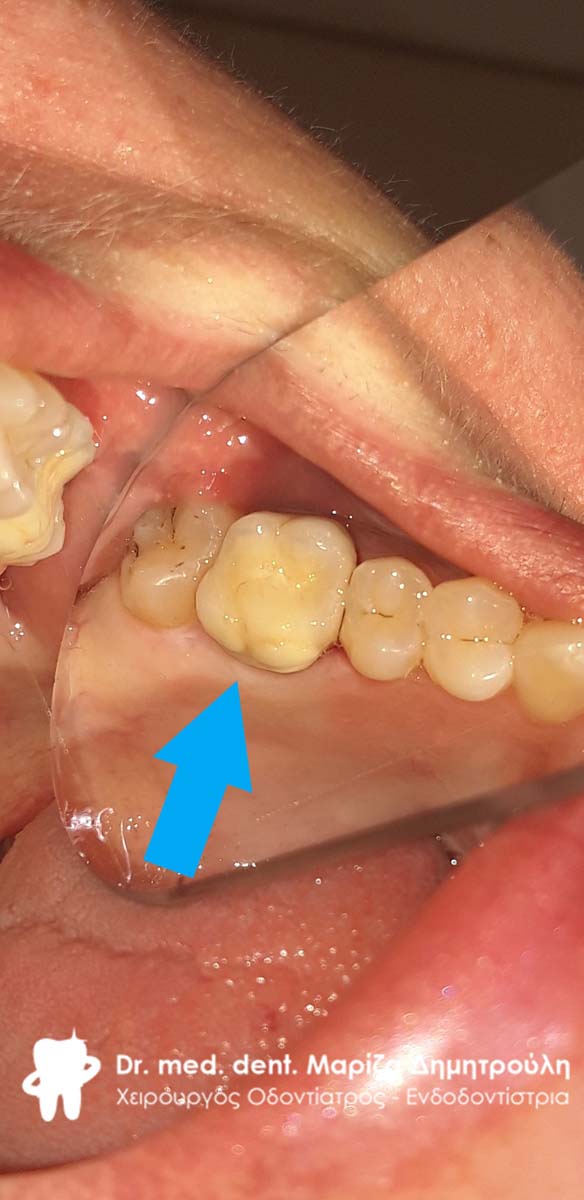

Αρχική εικόνα του παλιού μεγάλου σφραγίσματος

Κλινική εικόνα του μεγάλου οδοντικού ελλείμματος μετά την αφαίρεση του παλιού σφραγίσματος